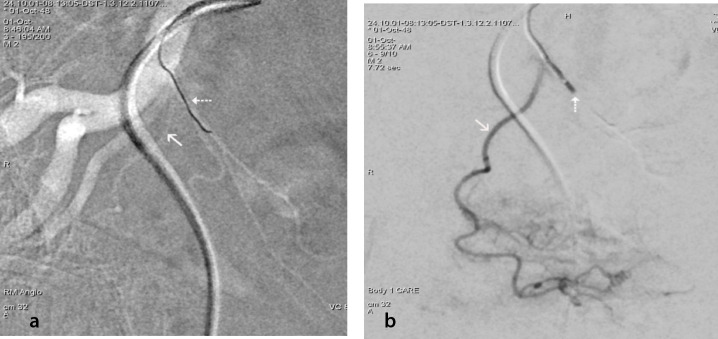

Prostatic artery (PA) origination from a common trunk with the superior vesical artery (SVA) is a frequent cause of technical difficulties in PA catheterization for PA embolization (PAE). These difficulties, which substantially increase the operative time, radiation dose, cost, and technical failure rate of PAE, can often be overcome by the utilization of a steerable microcatheter (MC) with a tip that can be manually adjusted at an angle that optimally conforms to the shape and origin of the common vesicoprostatic trunk. Adjunctive techniques that can be applied when the steerable MC fails to engage the PA include: 1) the protective temporary embolization of the SVA so that a permanent embolic can be redirected into the PA; 2) PAE via collaterals between superior vesical branches and the PA; and 3) embolization from a proximal position of the MC near the PA orifice to exploit preferential flow to the PA. In the authors' recent experience, the utilization of a steerable MC with and without adjunctive techniques (in 12 and 23 patients, respectively) resulted in a 35% increase in the technically successful embolization of PAs originating from vesicoprostatic trunks with no significant complications. Familiarization with alternative devices and techniques may substantially improve the technical outcome of PAE in cases with challenging arterial anatomy.